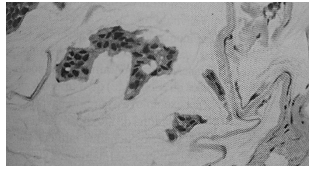

Assinale a alternativa correta que evidencia o diagnóstico para o quadro histológico ilustrado na figura abaixo.